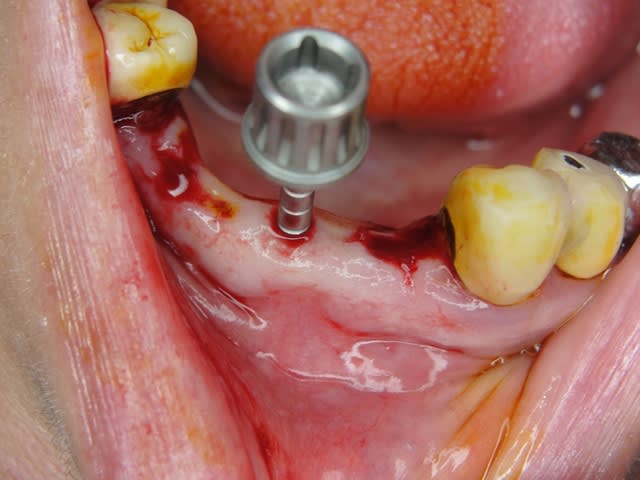

Maintenant concernant la demande de scans : je poste ce cas, une patiente vient me voir avec son scan car elle a consulté d'autres "spécialistes" et on lui refuse la pose d'implant secteur 4 où alors avec greffe préalable..Ca se discute..pas de temps à perdre je sais faire autrement..

Avec la chir trans gingivale technique MIMI ( Oui..un post sur la technique bientôt ..) j'ai pu placer deux 3,5/8mm..aurai je eu le meme résultat avec un lambeau..j'en doute..Les couronnes sont en titane. Recul clinique 2 ans ras. Simple efficace rapide moins onéreux satisfaisant pour le praticien et la patiente..